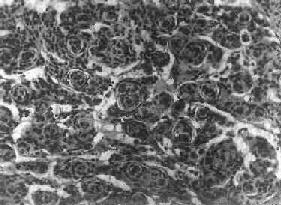

图16-24 多形性胶质母细胞瘤 发生于儿童、青少年的毛发细胞型星形胶质细胞瘤,生长极为缓慢。有报道称患者在不完全切除肿瘤后有带瘤存活达40年者。该瘤常位于小脑、第四脑室底部、第三脑室、丘脑和视神经。其形态特点是由双极性的肿瘤细胞两端发出纤细的毛发状突起。即使有毛细血管增生,本瘤的预后仍相对较好。 应该指出,同一肿瘤的不同区域,瘤细胞可有不同的形态特征,且分化程度也不尽相同,因此肿瘤的分型仅具有相对的意义。 星形胶质细胞瘤的细胞骨架含有胶质纤维酸性蛋白(GFAP),免疫组织化学染色呈阳性反应,是该肿瘤的特异标志。 2.少突胶质细胞瘤(oligodendroglioma) 约占颅内胶质瘤的5%,主要见于30~40岁的成人,男女发病的机会相等。本瘤绝大部分位于大脑半球皮质的浅层,尤以左额叶为多见。 肉眼观,肿瘤呈灰红色边界清楚的球形肿块,位于白质和邻近的皮质,并可累及软脑膜。囊性变、出血和钙化颇为常见,其中钙化灶对X线诊断有一定帮助。 镜下,瘤细胞大小均匀,形态单一,弥漫排列,胞核居中着色深,胞浆空,环绕胞核形成空晕。间质富有血管,有不同程度的内皮细胞增生。约有20%病例可出现瘤细胞钙化,其范围大小不一,其中7%为镜下钙化,有时钙化灶较大,可在X线片上显示出来。如肿瘤组织中混有星形胶质细胞瘤成分达到50%,则称混合性少突星形胶质细胞瘤。 本瘤生长缓慢,病程可长达10~30年,临床表现多为癫痫和局部性瘫痪。少数生长迅速,酷似多形性胶质母细胞瘤,预后不佳。 3.室管膜(细胞)瘤(ependymoma)起源于室管膜细胞,患者多为儿童和青少年。本瘤占颅内胶质瘤的5%~6%,多见于第四脑室,其次为侧脑室、第三脑室和导水管。脊髓病变多发生于腰胝及马尾部。 肉眼观,颅内室管膜瘤呈膨胀性生长,边界清楚,呈球形、分叶状或乳头状,肿瘤多在脑室内生长。切面灰白色,呈均匀或颗粒状,可发生灶性出血甚至坏死或囊性变,有时也可发现点状钙化。 镜下,瘤细胞大小形态一致,呈梭形或胡萝卜形,胞核圆或椭圆,染色质呈细颗粒状,核膜清楚,有核仁。瘤细胞胞浆丰富,突起明显。瘤细胞的排列有二种特征,一是环绕空腔排列成腺管状,形态上与室管膜腔相似,称为菊形团形成,另一是环绕血管形成假菊形团结构,瘤细胞有细长的胞浆突起与血管壁相连(图16-25)。细胞中有神经胶质纤维,以PTAH染色在个别细胞的腔面或胞核旁可见纤毛体,后者与纤毛运动有关,是室管膜细胞的特征性结构。此外,有时还可形成乳头状结构。发生在脊髓圆锥和终丝的肿瘤,乳头状结构轴心中的结缔组织往往富含粘液。

图16-25 室管膜瘤 瘤细胞为圆形或卵圆形,核染色质丰富,胞浆少,可见有细长的胞浆突起与血管相连,呈放射关,形成假菊形团 (二)髓母细胞瘤 髓母细胞瘤(medulloblastoma)好发于儿童,仅次于星形胶质细胞瘤而占第2位,其发生率占儿童颅内肿瘤的25%,发病年龄75%为15岁以下,偶见于成人,男性较女性为多(2~3:1)。 本瘤来源于小脑蚓部的原始神经上皮细胞或小脑皮质的胚胎性外颗粒层细胞,故本瘤主要见于小脑,在儿童多发生于小脑蚓部,在成人则多见于小脑半球。 肉眼观,瘤组织呈鱼肉状,色灰红。镜下,肿瘤由圆形、椭圆形或胡萝卜形细胞构成,胞核着色深,胞浆少而边界不清楚,有多少不等的核分裂像。细胞密集,间质中有纤细的纤维,血管不多。瘤细胞环绕一个嗜银性纤细的神经纤维中心作放射状排列形成典型的菊形团(图16-26),这对髓母细胞瘤的病理诊断有一定的意义。瘤细胞具有向神经元及神经胶质双向分化的潜能,既能向神经母细胞、节神经细胞分化,也能向胶质母细胞、星形胶质细胞分化。如瘤细胞侵入软脑膜,可在蛛网膜下腔脑脊液中广泛播散转移。